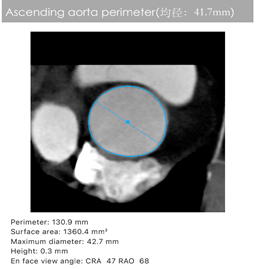

主动脉CT

陈凯明、刘浪教授团队术前总结了该病例特点:此例患者为单纯主动脉瓣返流,升主动脉直径41mm,瓣环周长79.8 mm,流出道周长86.2 mm,左心室扩大明显,特别是主动脉瓣环和瓣叶没有钙化组织, 升主动脉增宽, 喇叭口型左室流出道。这些特殊解剖特点使TAVR支架瓣膜锚定难度大,术中或术后可能出现瓣膜移位等严重并发症。这使得瓣膜的精准定位和释放极为关键。